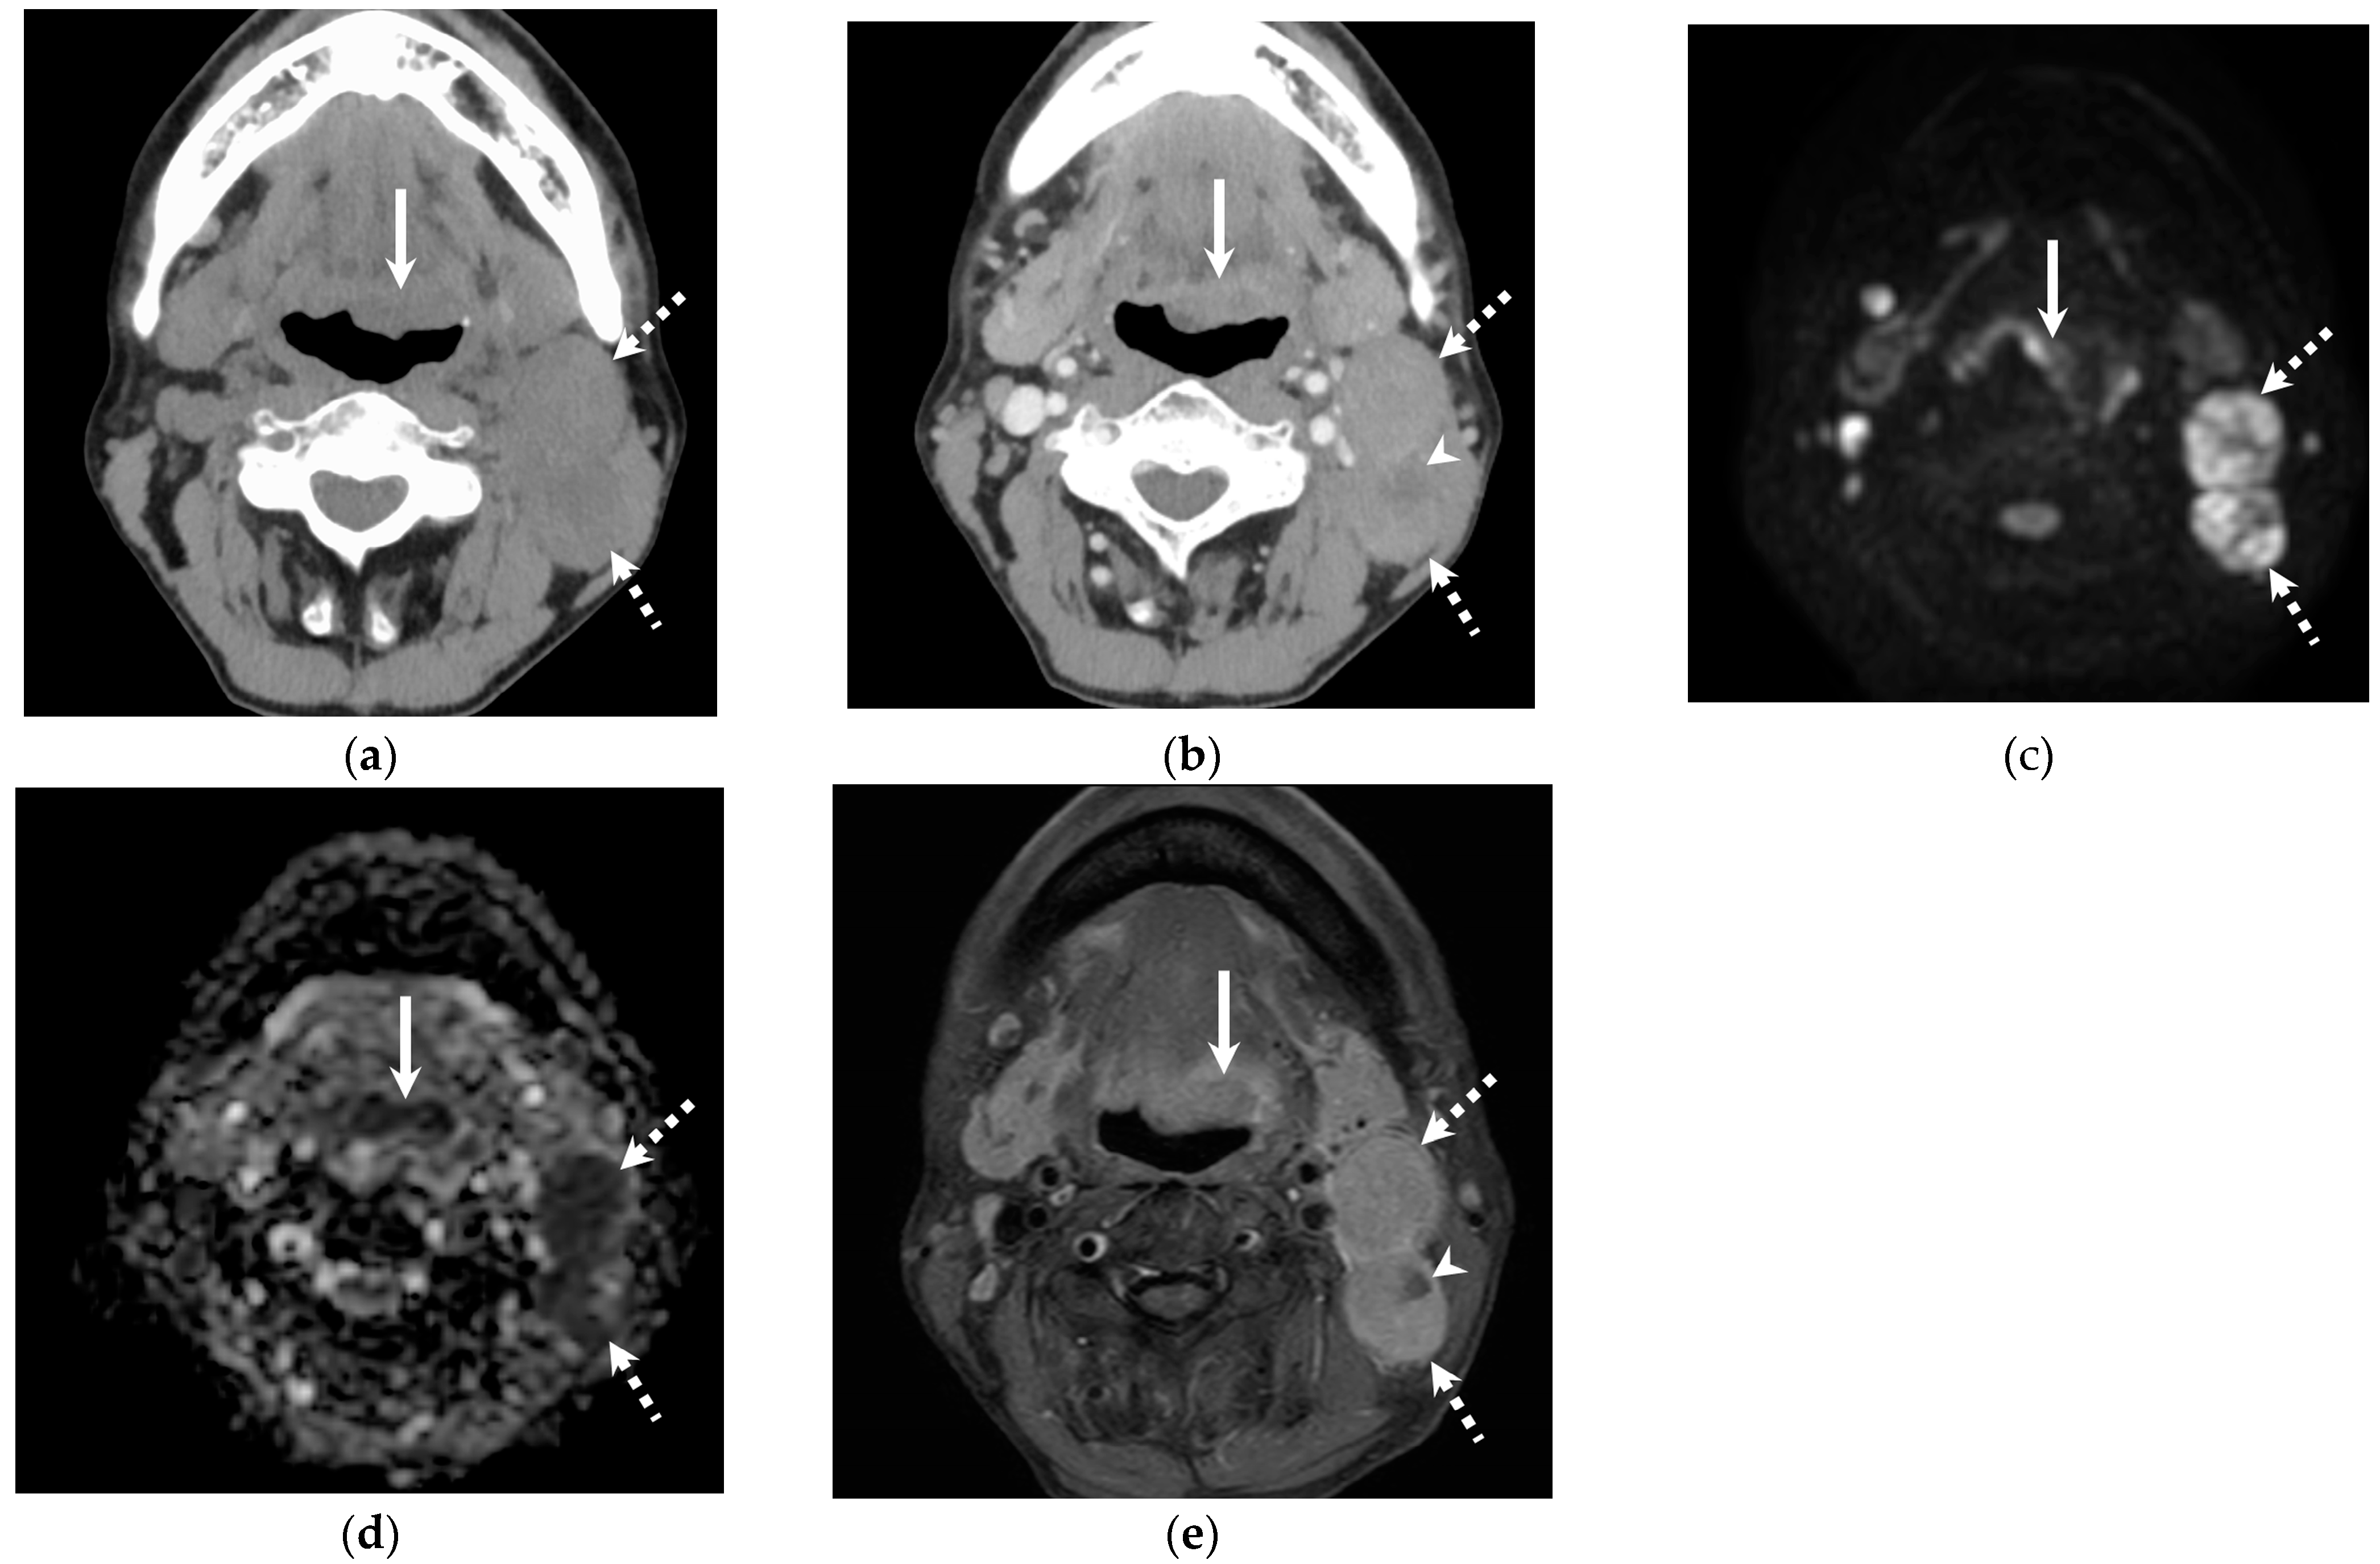

3.2. Quantitative and Qualitative Imaging Findings of the Primary Lesion

3.3. Quantitative Imaging Findings of Cervical Lymph Node Metastasis

3.4. Qualitative Imaging Findings of Cervical Lymph Node Metastasis

4. Discussion